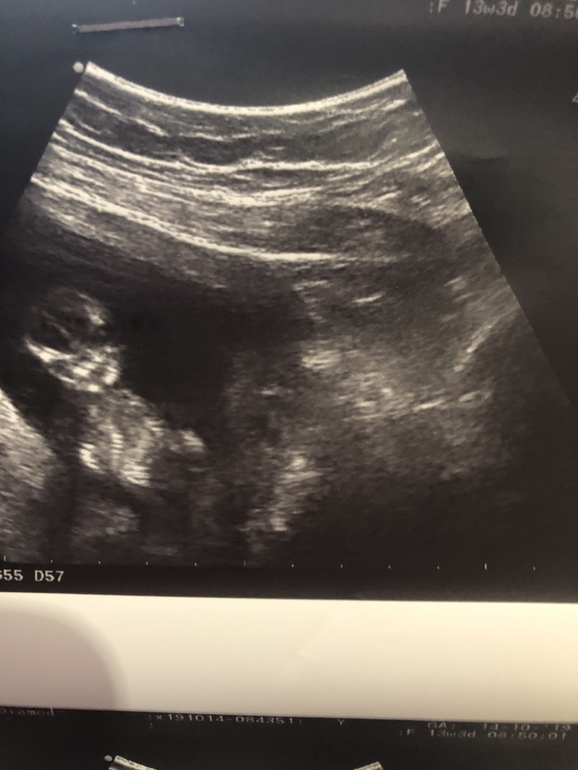

Беременность- 1 триместр ( только до 10 недель)Всем добрый день, девочки. Прошла первый скрининг. По узи все хорошо, все органы на месте. КТР 7,4, толщина воротникового пространства 1,8. Ребёнок хороший. По крови, думаю, все тоже будет хорошо.

Прикрепляю фото своей бусинки, кто там сидит пока не знаем, пойду на узи недель в 17 узнать, кто же у меня там поселился.